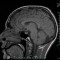

Pomalo zastrašujuće istraživanje kanadskih znanstvenika ipak će dati nadu onima čiji su najmiliji u komi. Naime, korištenjem funkcionalne magnetsko rezonantne tomografije, MRI-ja, liječnici su uspjeli uspostaviti kontakt s pacijentom koji je već 12 godina u komi. Pacijenta…

Najnoviji eksperiment kojeg su proveli britanski liječnici dokazao je da pacijenti koji se nalaze u komi ipak mogu komunicirati, odnosno odgovarati sa „da" ili „ne" na jednostavna biografska pitanja. Do fantastičnog se otkrića došlo…